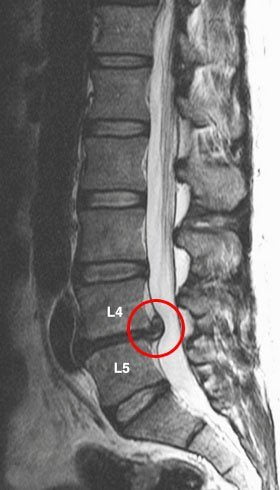

Грыжа в поясничном отделе позвоночника

Межпозвонковый диск между смежными позвонками может выпячиваться вправо. Межпозвонковая грыжа вызывает тупую, ноющую боль в пояснице из-за защемления спинно-мозгового корешка в узком фораминальном отверстии. Боль в пояснице справа может сопровождаться болями в ягодице и правой ноге, вплоть до стопы.